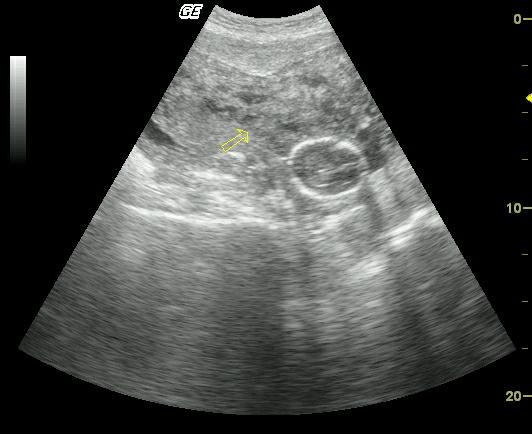

При заболеваниях миометрий неоднородный. Он может быть отечным. На УЗИ видна диффузная неоднородность.

- УЗИ матки, при котором рассматривается эхоструктура органа, и при не типичности показаний выносится предварительный диагноз;